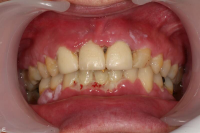

Akut inflammatorisk destruktiv sjukdom i gingiva och parodontium.

Karakteriseras av approximala nekrotiska och fibrintäckta sår (nedsmälta papiller) som är smärtsamma vid beröring och mycket lättblödande.

Patienten kan ha påverkat allmän tillstånd och ofta foeter ex ore.

I anamnesen förekommer ofta kombination av nedsatt immunförsvar, rökning, stress och dålig munhygien. HIV/Aids kan finnas som bakgrundsfaktor.